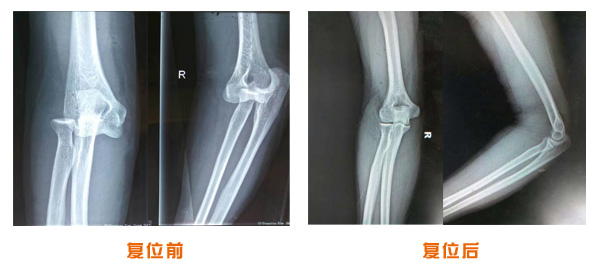

肥城市安駕莊梁氏骨科醫(yī)院是一所以梁氏手法正骨配合膏藥為特色的現(xiàn)代化專科醫(yī)院。

梁氏骨科術始創(chuàng)于清雍正年間,歷經(jīng)八代,至今已有三百年歷史。據(jù)1929年泰安縣志載“梁瑞圖先生,字增生,號蓮峰,安駕莊人,精岐黃并發(fā)明接骨,凡跌打車凡跌打車軋皮不破而碎骨者......【詳細】 |